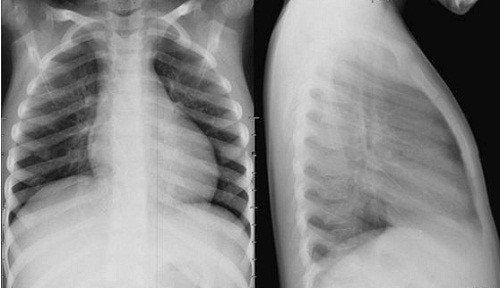

Phát hiện bệnh lý phổi phổ biến: Viêm phổi, lao phổi, tràn dịch màng phổi, u phổi, giãn phế nang, xơ phổi, khí phế thũng, COPD (bệnh phổi tắc nghẽn mạn tính)…

Theo dõi diễn tiến bệnh: Hữu ích trong quá trình điều trị các bệnh lý hô hấp, giúp đánh giá hiệu quả điều trị.

Hình ảnh rõ nét, độ phân giải cao: Cho phép quan sát chi tiết tổn thương nhu mô phổi, các vùng mờ, tổn thương dạng nốt, hang lao…